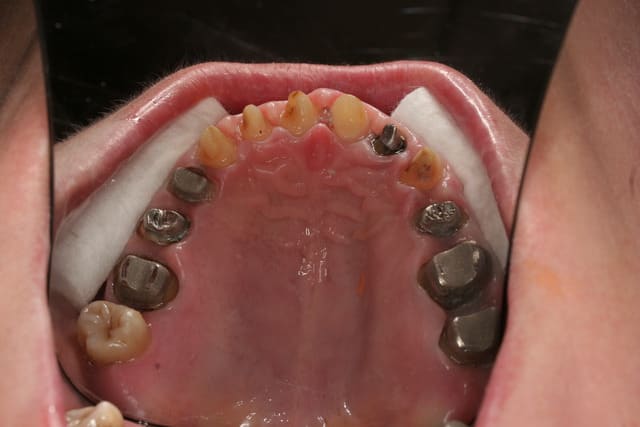

Donc la suite, évidement ortho: ingression du bloc incisivo canin sup avec ré alignement des arcades, extraction de la 14 nécessaire et ré alignement des milieux interincisif.

Pendant la finalisation du haut (axe mésio-disto incisif, à corriger à la fin pour faciliter gingivoplastie incisif sup). Il y a eu composite vestibulaire pelliculaire sous digue de 33 à 43, reprise soins et ancrage + provisoires 34,35, 36, 46; et composite sous digue 37 et 47.